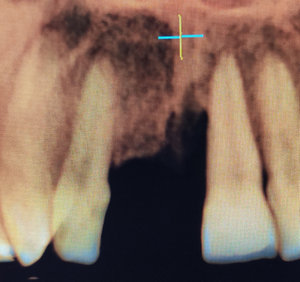

Добрый день. Мне в стоматологии сделали снимок зуба и сказали, что зуб надо удалять, так как вылечить не получится. Подскажите, так ли это? Может стоит обратиться к другим врачам? (фото зуба выслала на e-mail). Зуб № 46. На данный момент зуб не беспокоит. Три месяца назад был флюс, после разреза всё прошло. Антибиотиками не лечила, так как беременность. Сейчас срок 17 недель. Спасибо!

Да, к сожалению зуб необходимо удалить, так как на верхушках всех корней наблюдается обширное воспаление.